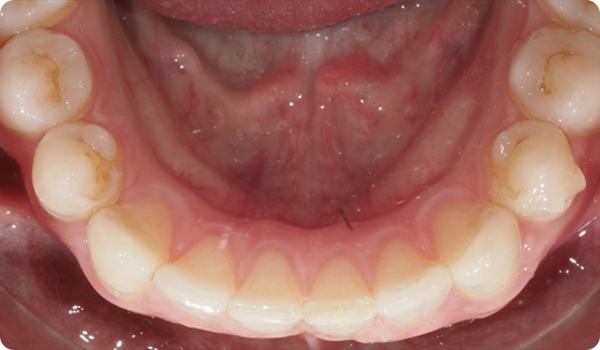

Designet til protetikere. Med små bevægelser korrigeres malpositioner og forbereder den mest egnede og konservative æstetiske behandling for dine patienter.

At justere tænder med Right er den perfekte og mest skånsomme forberedelse til fremtidig tandblegning eller facadebehandlinger, der vil perfektionere patientens smil.